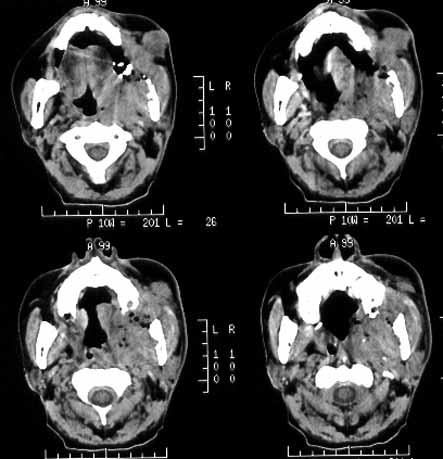

男性,60岁,鼻咽癌放疗后12年,5年前复发再行放疗后缓解。近期牙痛,牙龈活检见鳞癌细胞。

ct诊断:鼻咽癌复发,侵及左下颌骨、上颌骨及颞下窝。